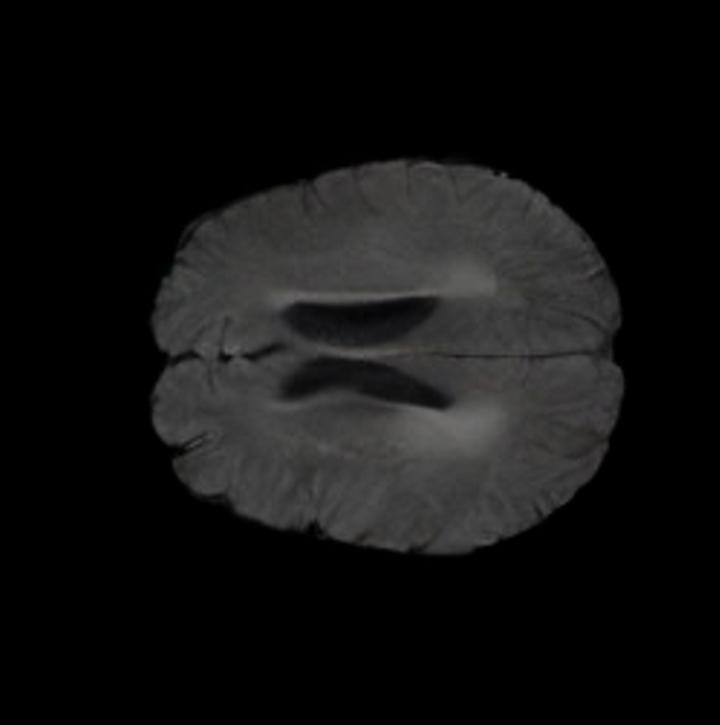

Our results unequivocally highlight the superior performance of X-Diffusion in terms of both qualitative and quantitative metrics. Representative MRI volumes generated by our pipeline, when juxtaposed with ground-truth images, showcased remarkable similarity, with even intricate physiological features like tumor information, spine curvature, and fat distribution being accurately captured.

Notably, X-Diffusion achieves sota dB for a few input slices while baselines require more than 60 input slices to achieve similar performance (Figure 7). The margin is more than 12 dB PSNR for the 1-slice input in both the BRATS and the UK Biobank benchmarks (see Table 1 and Figure 6). For reference, two randomly sampled MRIs from the UK Biobank would have a PSNR of 15.95 dB 0.36 (on 4800 randomly sampled examples). The slices from 3D reconstructed volumes at varying depths and axis of rotation visually match the ground truths (see Figures 5 and Figure 4). We also plot the error map (Figure 4) of such X-Diffusion generations to highlight the differences with the ground truth MRIs.

Brain Volumes Preservation. The generated MRIs by our X-Diffusion retain almost the exact same average brain volume vs of the real MRIs.

Tumour Information Preservation. For the brain tumor segmentation, we use a Swin UNETR model[27, 70], trained with random rotation, and intensity as data augmentation. In Figure 5, we highlight the tumor profiles of the generated MRIs compared to the ground truth tumour profile. In the test set with human ground-truth annotations (), the real MRI Dice score is 85.15 while the generated MRIs from a single slice have a dice score of 83.09. This shows how the generated MRIs indeed preserve the tumor information and can act as an affordable and informative pseudo-MRI, before conducting an actual costly MRI examination in hospitals.